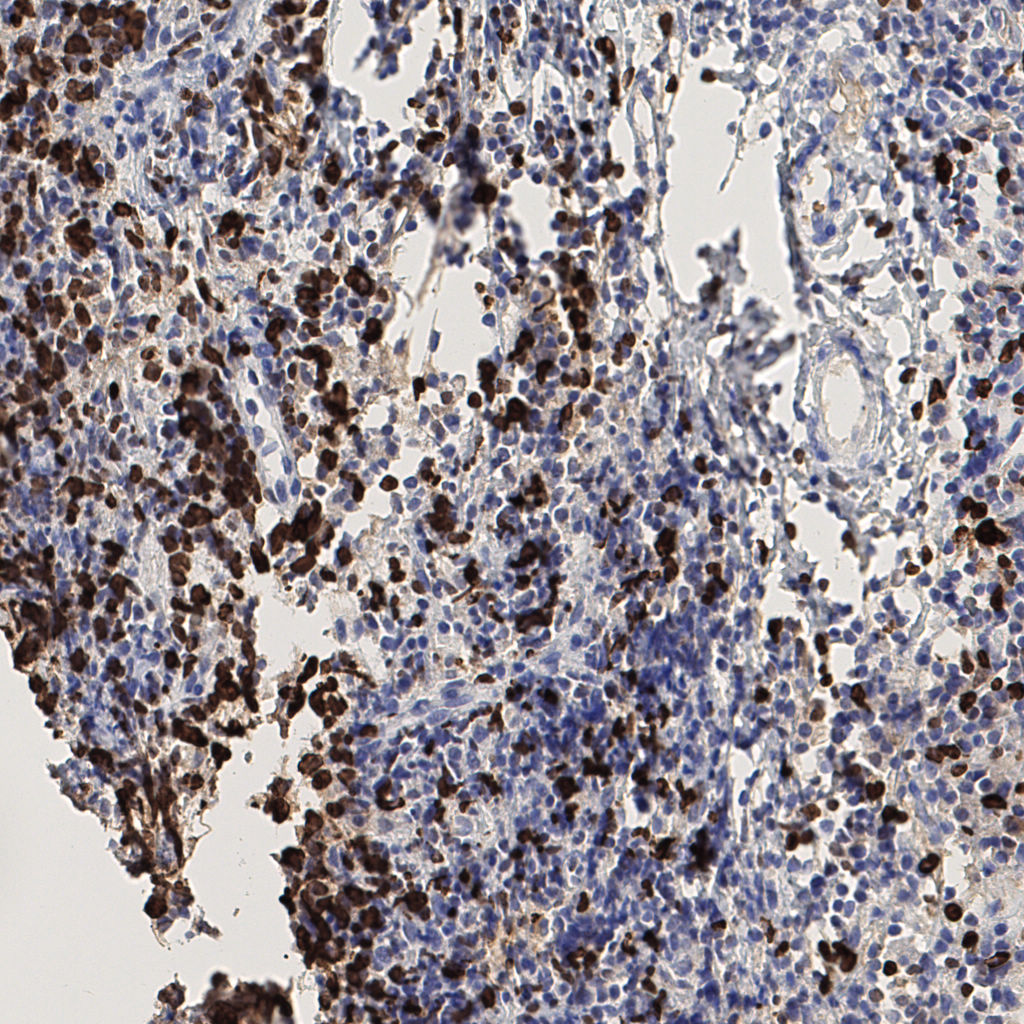

slice_42_6_x37632_y5376.png

slice_42_6_x37632...